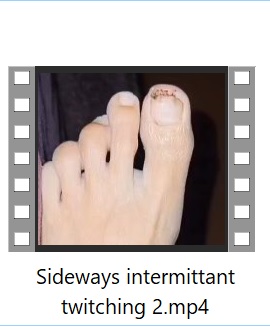

Patient is a 58 year old female physician with past medical history of high cholesterol, celiac disease and multiple food allergies who sustained an open crush fracture of the left big toe in June 2022 after a heavy double glass and metal shower door fell on her toe. She was seen in the ER and received wound care with tetanus booster and trephination of toenail. 2-3 days after injury intermittent twitching was noted in the small muscles surrounding the injured toe. One week after injury, twitching worsened around the medial left foot, progressed to the lateral toes of the left foot, then gradually progressed further up the left leg. Once twitching reached the gluteal muscles (ascending spread), it spread to the all extremities and back. There were several strong tonic contractions of gluteal muscles which lifted the patient off of the couch involuntarily. At this time patient had concern for tetanus and sought initial ID consult. Labs done included Creatinine Kinase which was 602 with normal CBC, CMP and negative blood cultures.

Patient was hospitalized in August 2022 for IV (Intravenous) metronidazole which helped reduce (but not eliminate) symptoms for about one month. MRI of the left toe showed still healing fracture and ortho consult did not recommend surgical intervention at that time. Multiple neurology consults were obtained to rule out neurological cause of symptoms given the unusual presentation and all neurology consults felt this was not primarily a neurological issue and she was referred back to Infectious Disease for management. EMG & MRI of the brain were done and were both normal. (Patient was advised to continue benzodiazepine during initial EMG so any possible exaggerated F-response and spasms were suppressed by benzodiazepines during the EMG). During all physical exams involuntary muscle spasms/ twitching of the left foot/toes were noted involving both agonist and antagonist muscles.

1) Videos of Left Toe & Foot Spasms/Twitching: